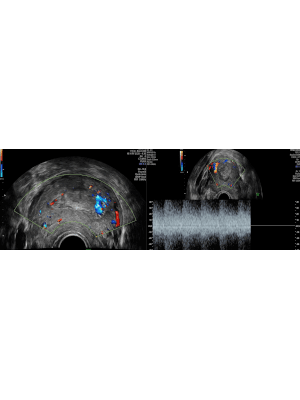

Ultrasound diagnosis of retained pregnancy tissue

Retained pregnancy tissue (RPT) is a common complication affecting many women following delivery, miscarriage and termination of pregnancy. The use of transvaginal ultrasound remains the most accurate imaging modality for assessing symptomatic women. However, diagnostic accuracy is heavily dependent on a number of factors. Prompt, accurate diagnosis of RPT is essential to identify women who require intervention and to prevent immediate and long-term physical and psychological morbidity. This article will present helpful ultrasound appearances when assessing women for RPT, and the common dilemmas and pitfalls.